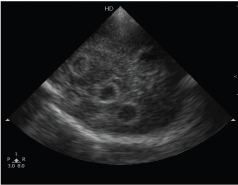

At admission, baby was febrile (101.90F), deeply icteric, sick looking and anterior fontanelle was full. Laboratory investigations showed haemoglobin of 12.5 gm/dL, leucopenia (WBC: 3200/mm3), thrombocytopenia (platelets: 1.1 lakhs/mm3) and positive septic screen (CRP: 65.4 mg/l). Bilirubin was 24.6 mg/dL with direct fraction of 1.2 mg/dL and there was evidence of haemolysis due to blood group incompatibility (baby’s group: B+; mother’s group: O+; reticulocyte count 12%; direct Coombs test positive). Baby was given intensive phototherapy, antibiotics (cefotaxime, amikacin) and ionotropic support. Head ultrasound at admission showed multiple cerebral abscesses in bilateral frontal and parietal lobes [Table/Fig-1]. Cerebrospinal Fluid (CSF) was turbid and showed 720 cells (neutrophils 90%; lymphocytes 10%), proteins 382 mg/dL and glucose 10 mg/dL (blood glucose: 64 mg/dL). Gram-stain showed Gram-negative intracellular diplococci.

Ultrasound brain at admission showing multiple cerebral abscesses